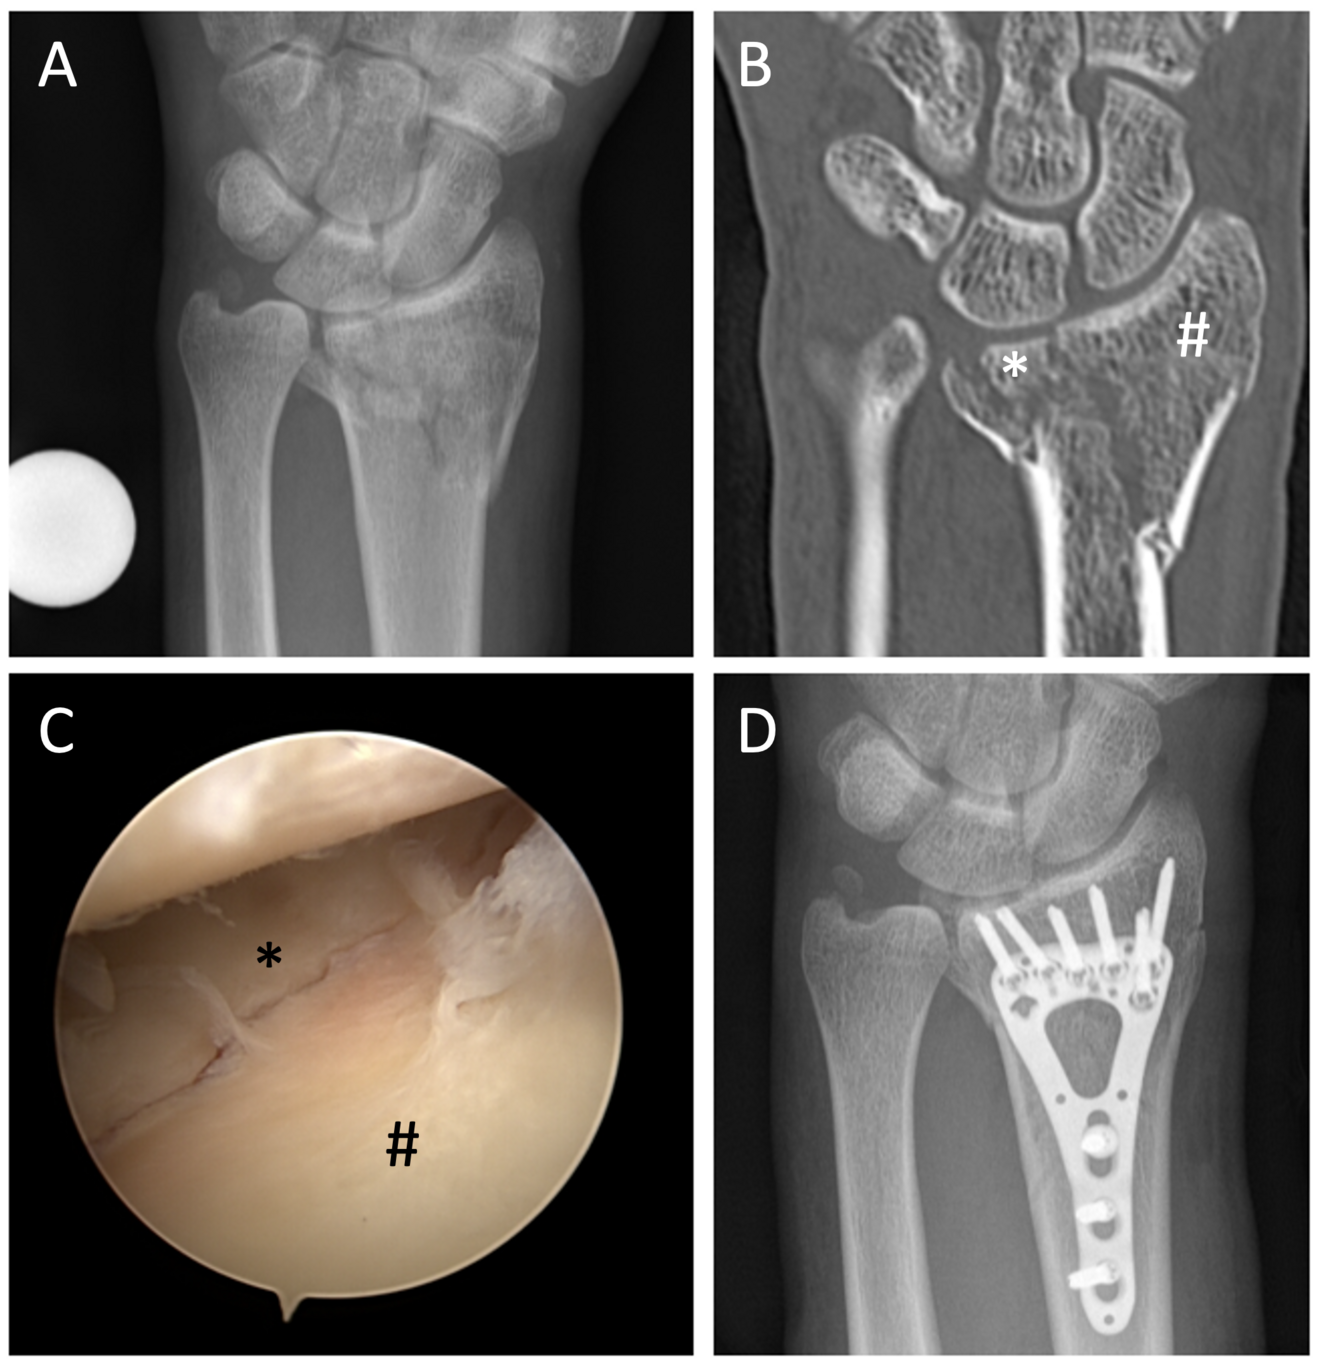

Knapp 40-jähriger Patient mit einer intraartikulären Fraktur mit grossem Fragment des Processus styloideus radii (#) und einem «die punch»-Fragment (*) in der Fossa lunata (Abb. 1A und 1B). Nach Reposition konnten eine artikuläre Kongruenz der ulnaren Säule bzw. der Sigmoid Notch anhand einer arthroskopischen Beurteilung bestätigt werden (Abb. 1C). Durch das periphere Avulsionsfragment des Processus styloideus ulnae wurde keine Instabilität des DRUG erwartet. Jedoch zeigte sich eine kleine zentrale TFCC-Läsion (Typ 1A nach Palmer). Nach knöcherner Konsolidierung der Fraktur (Abb. 1D) konnte bei persistenten ulnaren Schmerzen eine therapeutische Infiltration des TFCC erfolgreich durchgeführt werden.